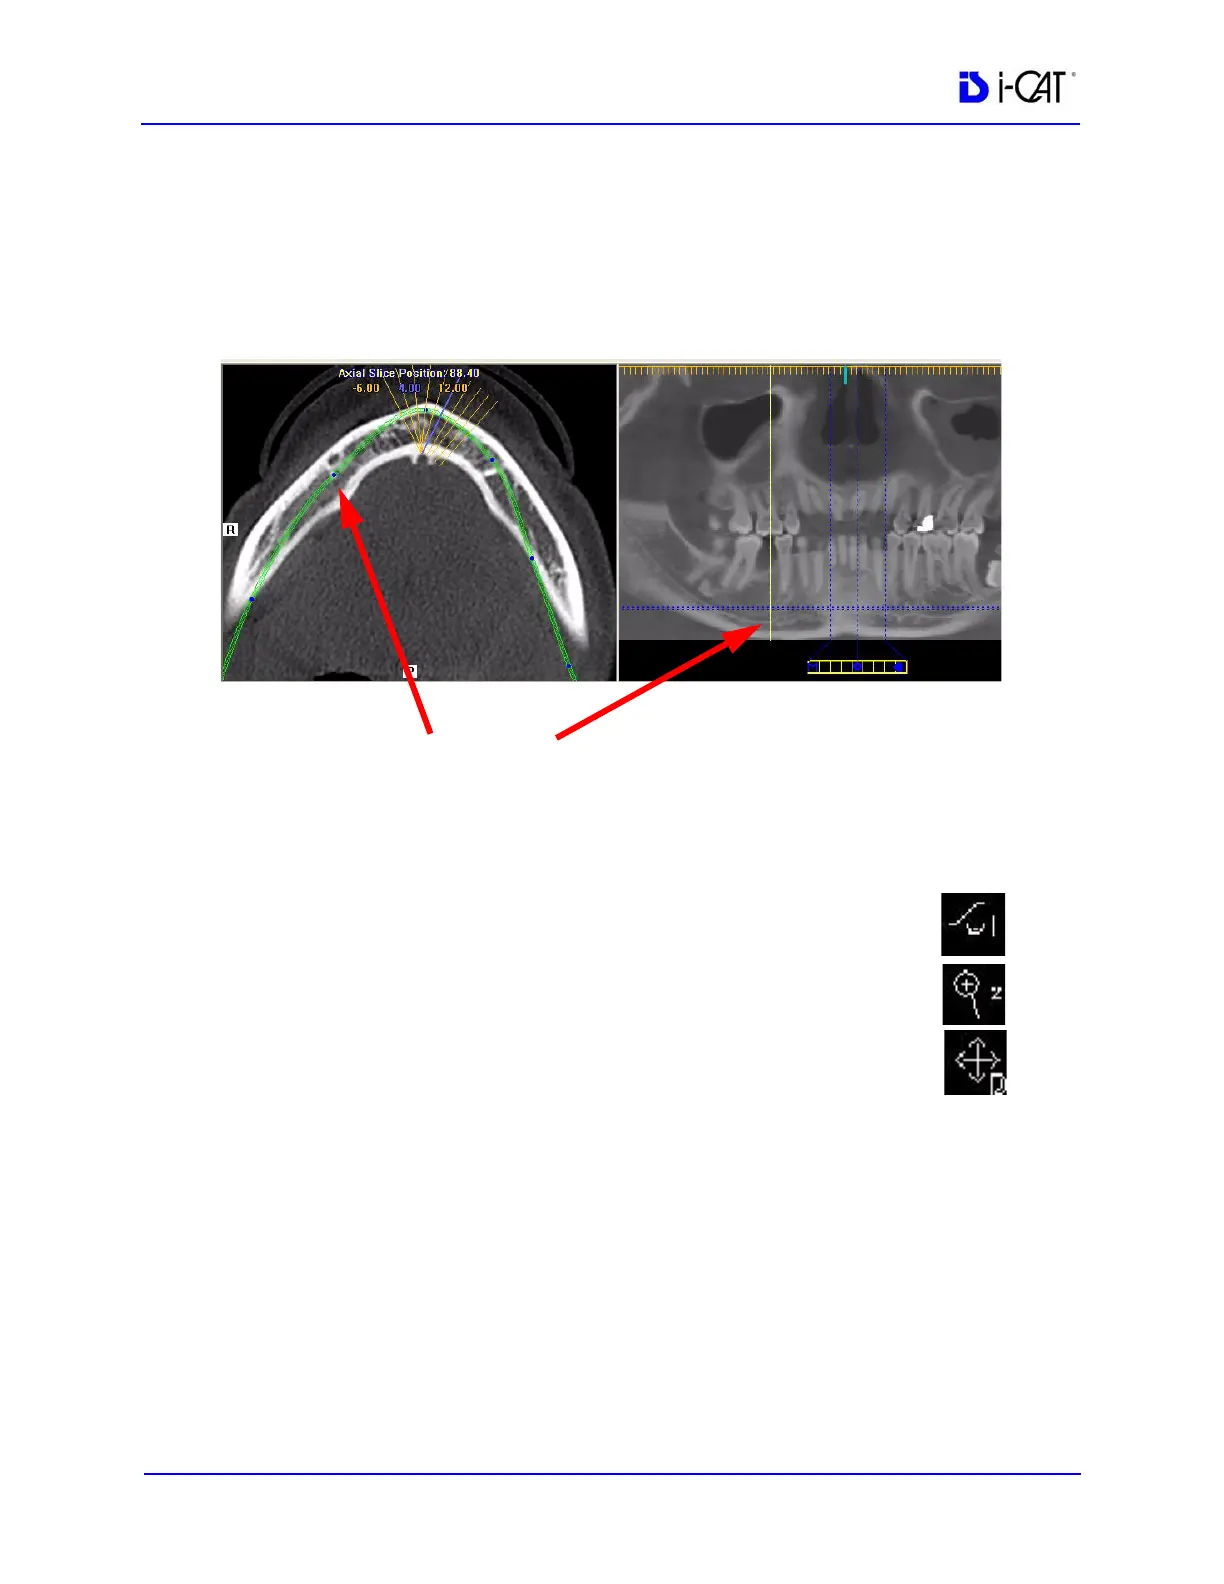

5. On the axial slice position view, click and drag the blue dots to

adjust the contourline to bring the nerve canal(s) into clear focus.

When you hover on a dot, a yellow line is displayed on the

panoramic map view showing the location you are adjusting.

Continue buccal-lingual adjustments as needed along the

contourline to clearly visualize the nerve canal(s).

BLUE DOT ON AXIAL SLICE POSITION VIEW CORRESPONDS

TO YELLOW LINE ON PANORAMIC MAP VIEW